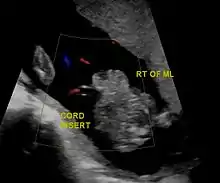

In the developed world, around 90% of cases are identified during normal ultrasound screens, usually in the second trimester.[17]